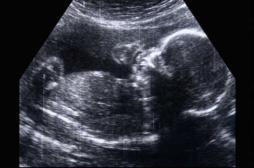

bébé

EN DIRECT